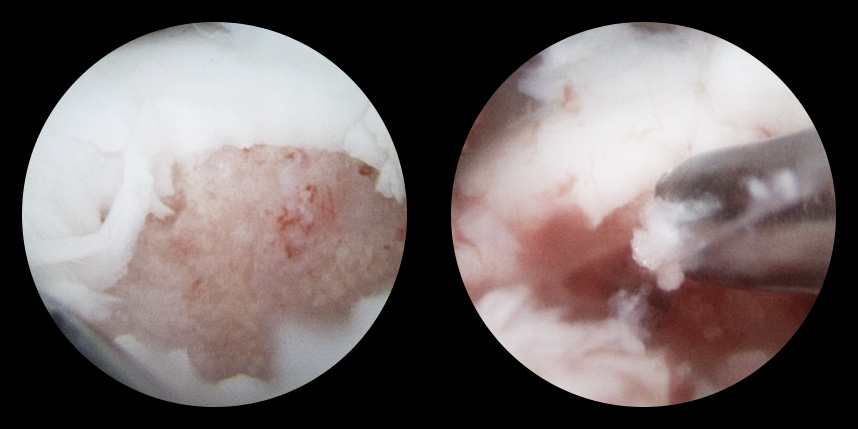

연골손상의 단계를 결정할 때 사용하는 ICRS 단계에서 3단계 미만의 연골손상에 사용하는 방법으로 울퉁불퉁한 표면을 다듬어 주는 정도의 수술법입니다.

4단계 이상일 경우 미세천공술을 기본으로 시행하며, 미세천공술로 나온 본인의 골수줄기세포와 함께

연골 생성을 촉진할 수 있는 “재료”를 같이 주입하는 치료를 시행합니다.

손상된 연골 부위에 작은 구멍을 뚫어 골수에서 나오는 줄기세포를 이용하여 연골 재생을 유도하는 방법으로 근본적으로 섬유연골(정상연골보다는 약한 연골)로 재생된다고 알려져 있습니다.

특수하게 농축하여 제작된 6% 콜라겐(리젠실603) 또는 9% 콜라겐(이엔카티)을 천공술을 시행한 부위에 덮어 주어 미세천공술 단독보다 좋은 치료 결과를 기대할 수 있습니다.

본원에서는 미세천공술, 콜라겐주입술, 카티스템 치료를 주로 하고 있습니다.

연골재생술 진행

(미세천공술 + alpha)

타병원 미세천공술 실패 후 통증으로 내원하신 사례